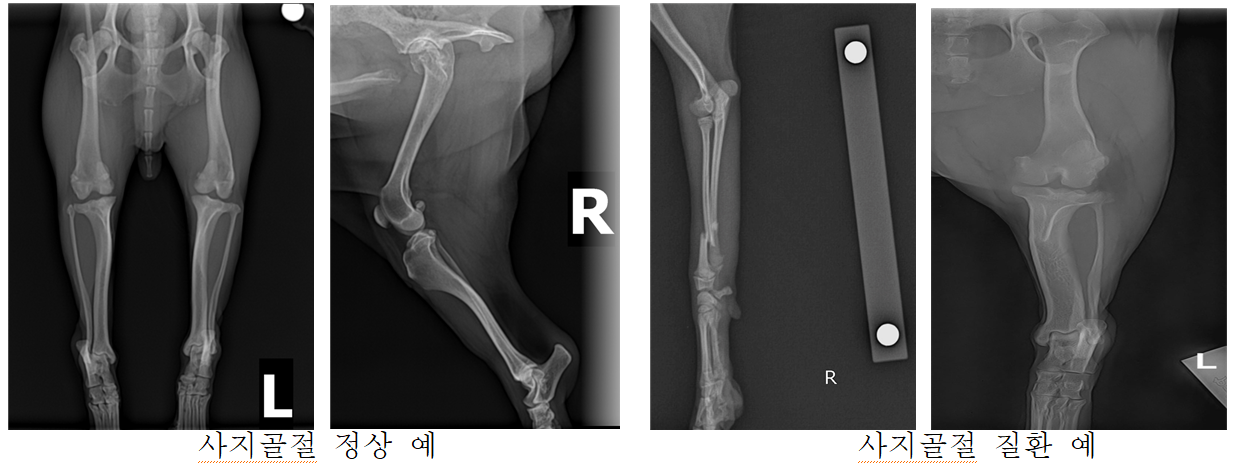

반려동물 질병 검사 과정에 필요한 엑스레이, 초음파 등의 영상을 기반으로 근골격계 질환 진단에 활용하는 AI 기술 개발을 위한 데이터

- 반려동물 질병진단 서비스를 제공하기 위해 AI 학습 과정에 필요한 다량의 고품질 데이터 확보 - 확보된 다량의 고품질 데이터를 활용해 학습한 질병진단 AI 모델 기반의 서비스를 토대로 반려동물 산업 분야의 의료서비스 활성화

데이터 구축 규모 구분 구축량 질환데이터 정상데이터 질환비율 (건) (건) (건) (%) Mu01(골격계종양) 31,597 170 31,427 0.50% Mu02(사지골절) 27,141 1,323 25,818 4.90% Mu03(갈비뼈골절) 44,071 763 43,308 1.70% Mu04(엉덩관절탈구) 11,059 1,072 9,987 9.70% Mu05(슬개골탈구) 12,600 4,737 7,863 37.60% Mu06(전십자인대파열) 14,342 1,187 13,155 8.30% Mu07(추간판질환) 19,332 1,145 18,187 5.90% 합계 160,142 10,397 149,745 6.50% -